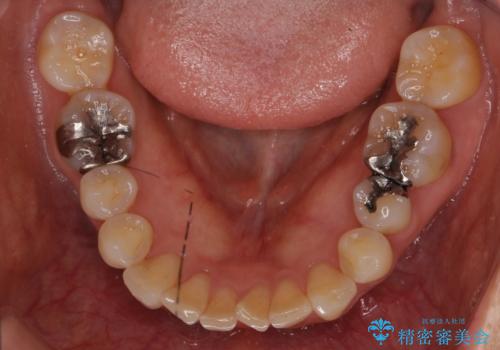

- 銀の詰め物が気になるとのことで来院。

2本隣り合っているつめものを、同時にやりかえをしました。